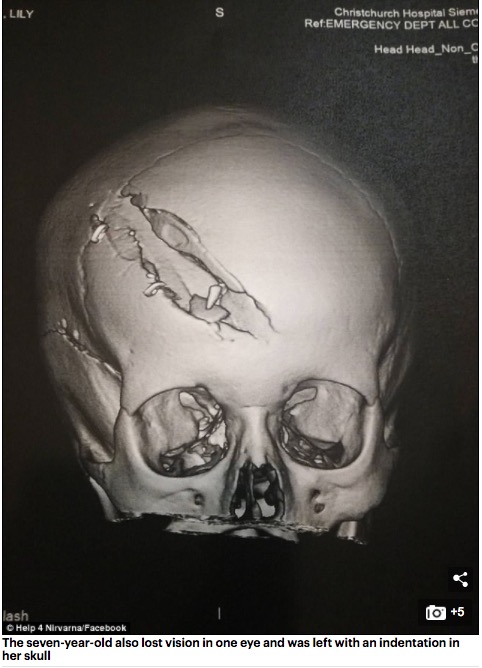

这个小女孩在车祸中受了重伤,其中包括骨折,踝关节断裂以及两根股骨骨折,她的一只眼睛在这次事故中失明,头骨也留下了一道凹陷。